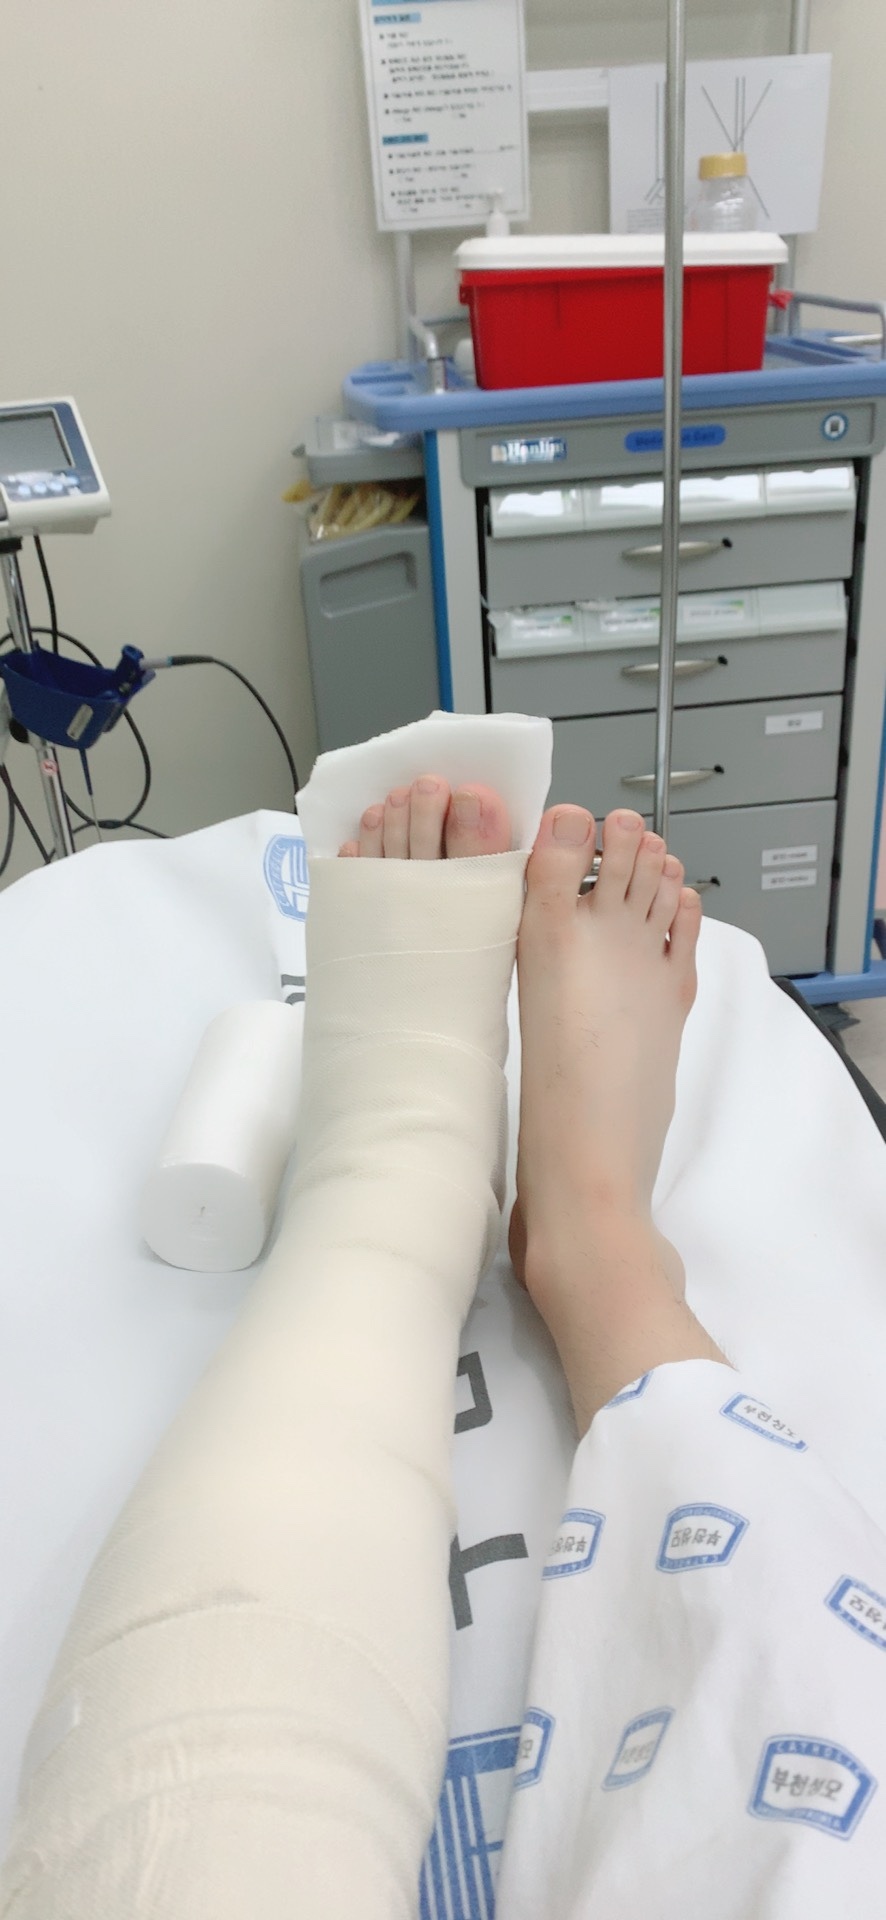

다리를 전체를 고정하는 게 아니라 이렇게 반만 부목 형태로 고정하는 것을 의미한다.

저 하얀색 지지대가 반깁스라고 하는 스프린트다

다리 반깁스의 주의점 : 반깁스(스프린트)를 통한 다리깁스 시 뒷꿈치 욕창의 문제

반깁스 시술이나 깁스 시술 시 뒷꿈치가 깁스에 눌려

욕창이 생기는 경우가 있다

욕창발생 시 통증을 유발하고 멍이들거나 피부괴사등의 문재가 발생하시때문에

뒷꿈치의 욕창을 방지하기 위해 솜붕대를 두껍게 감거나, 폼패드를 요즘에는 많이 사용하고 있다,

그냥 처음에 스프린트로 모양을 만들떄 솜붕대를 감소하거나 아래의 폼패드를 하고 모양을 만들고

굳은다음에 다시 붕대를 감으면 뒷꿈치 통증은 그나마 덜하다. 이게 너무 스프린트와 뒷꿈치가 딱붙어도 문제라

스프린트 시술시 솜붕대를 두껍게감고 스프린트를 경화 (굳혀야) 욕창이 덜 잘생한다 눌리지않고 여우가 있기 때문.

대학병원급은 다리의 경우 솜붕대를 감고 반깁스를 제작하는경우가 많은 것 같았다.